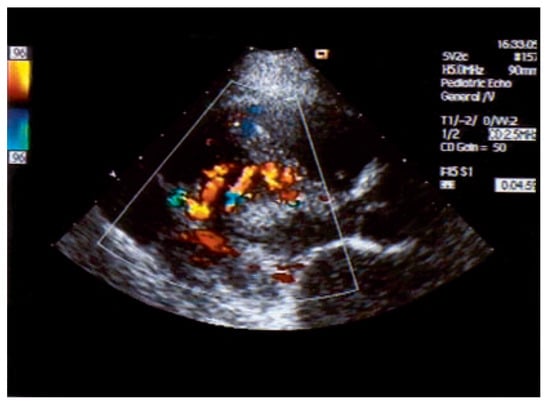

An otherwise healthy 13-year-old girl was referred to the pediatric cardiology outpatient clinic for evaluation of a newly observed systolic murmur. She was normally physically active without symptoms on exertion except for one episode of syncope two months earlier. She then was riding a bike and on climbing off the bike she was observed to hyperventilate, had parestesias of both hands followed by a short loss of consciousness. Family history was negative for any cardiac event. Clinically the systolic murmur was judged a functional ejection murmur but an Echo was done and revealed an enlarged (6 mm) right coronary artery (Figure 3) with huge collaterals especially in the septal region (Figure 4), the origin of the left coronary artery was seen in the pulmonary trunk with turbulent retrograde flow in the color Doppler (Figure 5). LV ejection fraction was 68% but the LV was slightly dilated with a mild mitral regurgitation. Cardiac catheterisation confirmed the suspected anomalous origin of the left coronary artery from the pulmonary trunk (Figure 1 and Figure 2), the patient was advised to undergo surgical correction with reimplantation of the left coronary artery in the aorta.

Figure 2. Lateral view of selective right coronary artery injection: the very tortuous course of the RCA is seen as well as the opacification of the pulmonary artery trunk with the left coronary artery ostium at its inferior aspect.